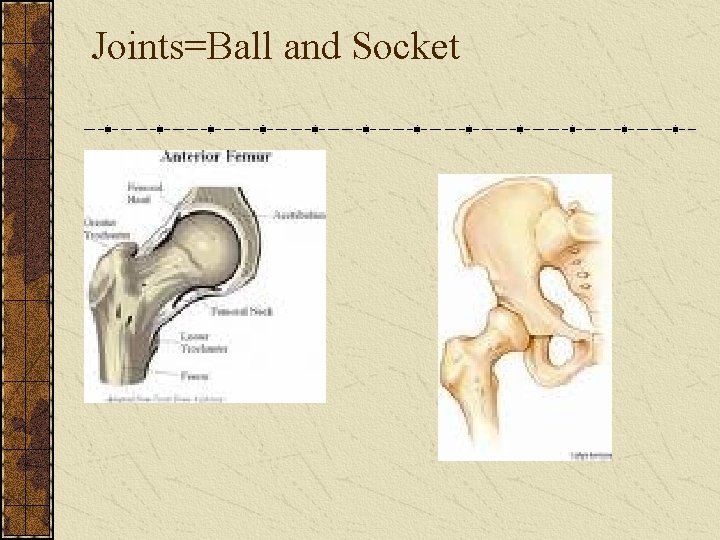

Joints Immovable joints Sutures=skull joints Movable joints Ball-and-socket joints • Hip Hinge joints • Elbow Saddle joint • Base of thumb

Joints=Ball and Socket